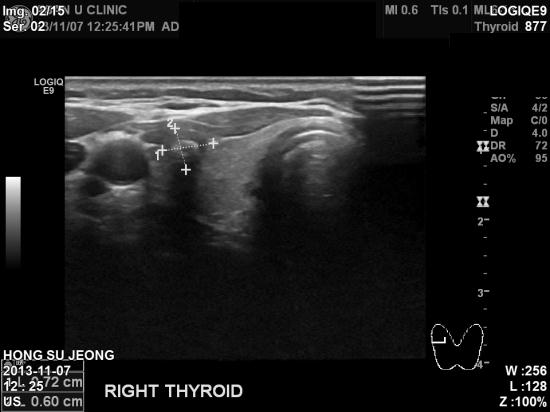

본원에서 갑상선 초음파와 혈액검사를 실시하였고,

혈액검사결과는 정상수치로 나왔으나 초음파상 이상소견이있어

세침흡입검사 시행결과 갑상선유두암으로 진단되었습니다.

혹크기는 1cm 미만으로 크기가 작고, 주위 임파선으로의 전이여부가 없어 보여